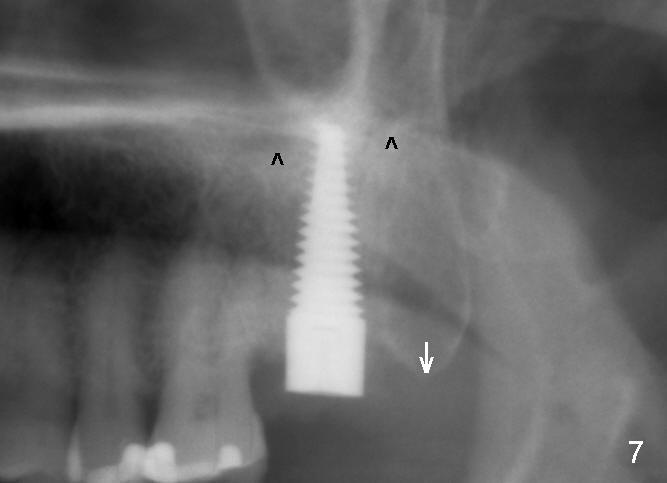

A 57-year-old lady presents for abscess buccal to the tooth #15 (Fig.1 A). Mesial and distal to the occlusal composite (Fig.2 C) is a crack line. In addition to long furcated roots, the upper border of the bone is not shown in this preop PA (arrow). Fig.3 is taken to show a thin septum surrounded by the mesiobuccal (MB), distobuccal (DB) and palatal (P) sockets (Fig.3). Osteotomy is initiated in the septum by 1.2 and 1.5 mm pilot drills, followed by 2,3,4 mm rounded tapered osteotomy at the depth of 17 mm. Nose blowing test is carried out after each step with negative result. Stability is achieved when a 4.5 mm tap is inserted at 17 mm, but the upper end of the tap is not visible (Fig.4,5). When a 5 mm tap is placed, stability is decreased, probably because the coronal end of the septum starts to break down (due to expansion). To re-gain stability, the 5 mm tap needs to go deeper. A 6 mm tap also achieves satisfactory stability at 20 mm. When the tap is removed, there is no air leakage. A 6x20 mm implant is placed with insertion torque > 60 Ncm; the upper end of the implant is still out of view in PA (Fig.6). Another problem is that the implant needs to go deeper to obtain sufficient occlusal clearance. The lower first molars and the 2nd premolars are missing. A panoramic X-ray has to be taken to show the apical end of the implant: ~ 3 mm into the sinus (Fig.7 ^). The maxillary tuberosity appears to grow downward (arrow). In other word, the tooth #15 appears to have been intruded due to overloading.